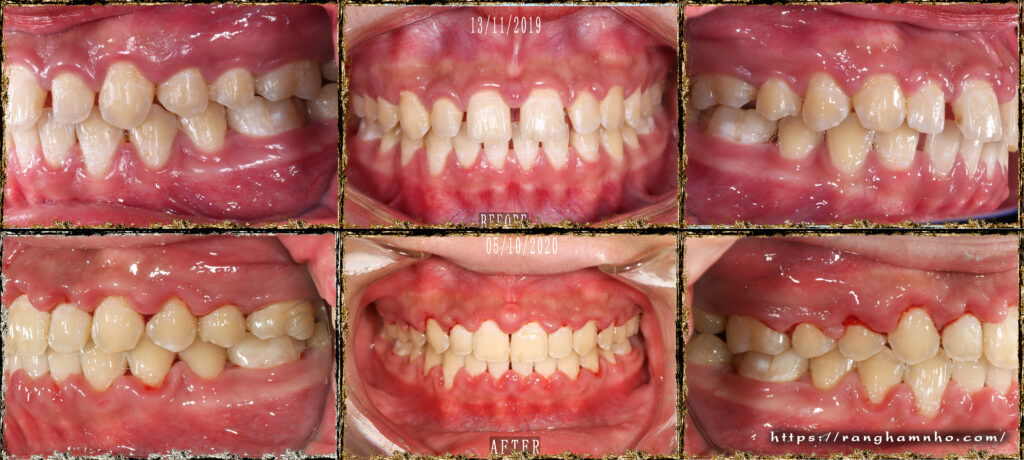

Bệnh nhân nữ sinh năm 2004 đã được điều trị tại 1 cơ sở nha khoa khác hơn 1 năm nhưng không cải thiện được tình trạng răng thưa, tình trạng việm lợi & hôi miệng cũng làm người nha BN lo lắng, không yên tâm trong công tác điều trị, cuối cùng có những khúc mắc ngoài lề giữa bác sĩ và người nhà nên BN không tiếp tục điều trị ở cơ sở cũ mà chuyển cơ sở điều trị khác.

Đánh giá: một trường hợp khe thưa răng cửa giữa hàm trên rất hay gặp trên lâm sàng, nếu không đánh giá đúng tính hình có thể rất dễ bị tái phát do vấn đề khớp cắn, khi đong khe thưa không căn chuẩn thì đường giữa hai răng cửa hàm trên sẽ lệch so với đường giữa mặt (lệch đường giữa hàm trên) và đường giữa hàm dưới có thể không thẳng đường giữa hàm trên.

Phương án: đóng khe thư nhóm răng cửa trước, đánh giá cẩn thận khi đóng khe thưa răng cửa giữa hàm trên và hàm dưới kĩ lưỡng, đưa đường giữa về vị trí chuẩn, sau đó mới đóng hết khoảng và tinh chỉnh khớp cắn.

Kết quả: đường giữa đẹp, khớp cắn ổn sau 1 năm điều trị. Tuy nhiên, BN đeo niền lâu & yếu tố tuổi dạy thì làm tình trạng việm lợi- phì đại lợi tồn tại. BN được tháo mắc cài, hướng dẫn CSRM kĩ lưỡng kèm mát xa lợi, đeo hàm duy trì máng trong. Kết qảu tái khám rất ổn sau 6 tháng.